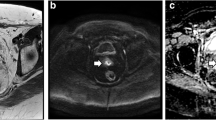

Tumour delineation

One radiologist (R1), board-certified with > 10 years’ experience in abdominopelvic MRI, manually drew volumes of interest (VOIs) using the freehand selection tool on ImageJ (ImageJ 1.52a, National Institutes of Health) to encompass the whole primary tumour on T2W images b1000 DWI images with reference to the T2W images and D parametric maps of pre- and post-CCRT images (Fig. 1). The radiologist was given both sets of images and was aware of the sequence of the MRI examinations. The T2W VOIs were used to measure tumour volume, while the DWI VOIs were then propagated to co-registered D and f parametric maps estimated with the full BVD and optimised subsample BVD (Fig. 2). The radiologist was also asked to measure the length of the tumour’s longest axis on T2W images for treatment response assessment.

Representative pre-concurrent chemoradiotherapy (pre-CCRT). a Diffusion-weighted images (DWI), b = 1000 s/mm2 that were also overlaid with parametric maps of (b) pure diffusion coefficient (D) and (c) perfusion fraction (f) over the tumour as well as the corresponding (d–f) post-CCRT images and parametric maps. The cyan regions of interest (ROI) represent the first delineation by the senior radiologist on DWI which was copied to the D and f parametric maps

To measure observer repeatability, a second radiologist (R2), with 3 years’ experience in abdominopelvic MRI, delineates VOIs on pre- and post-CCRT MRI examinations as previously described. Additionally, the patient order was randomised and R1 was asked to delineate another set of VOIs on pre- and post-CCRT MRI examinations after a 1-month interval for all patients (Fig. 3).

Representative diffusion-weighted images (DWI) b = 1000 s/mm2 (a) before pre-concurrent chemoradiotherapy (pre-CCRT) and (b) after CCRT (post-CCRT). Regions of interest (ROIs) were drawn twice by a senior radiologist and once by a junior radiologist on both (c) pre-CCRT and (d) post-CCRT images. The segmentations by the senior radiologist are denoted by the cyan ROIs during the first reading session, and by the yellow ROIs for the second session. The delineations by the junior radiologist are denoted by red ROIs